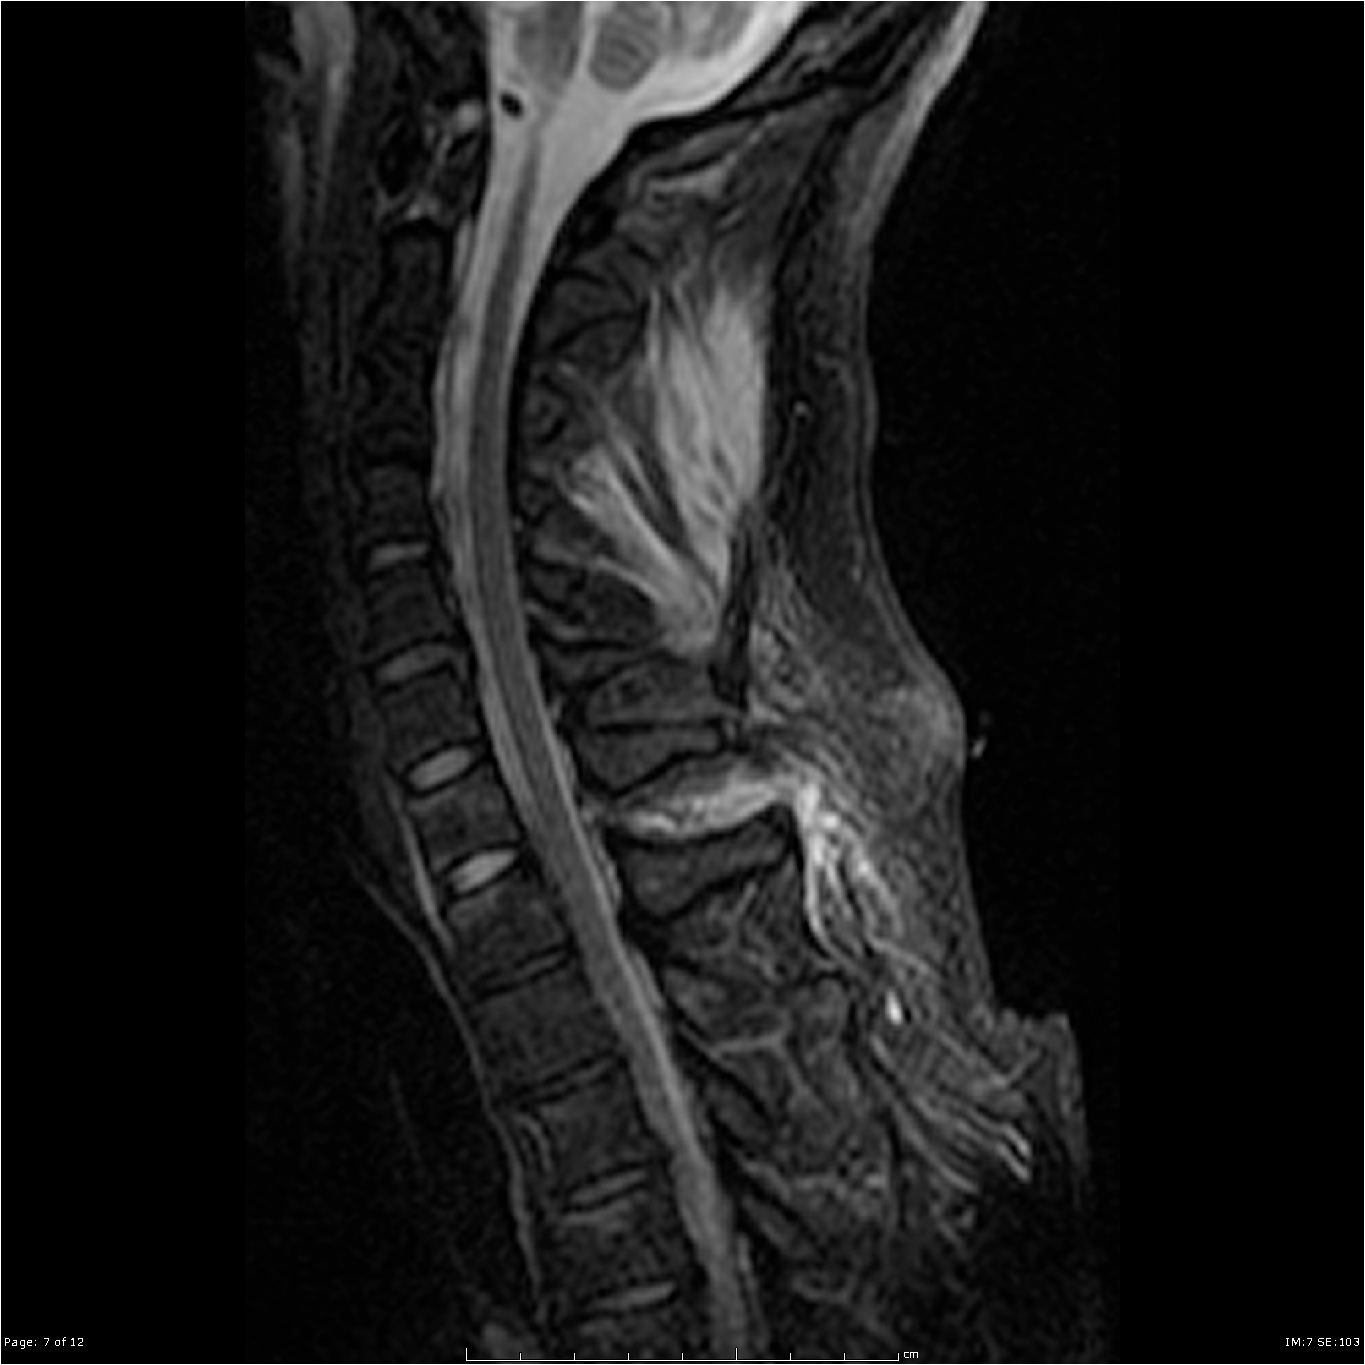

MRI of the neck showing Ligamentum flavum tear from C7-T1 not seen on CT